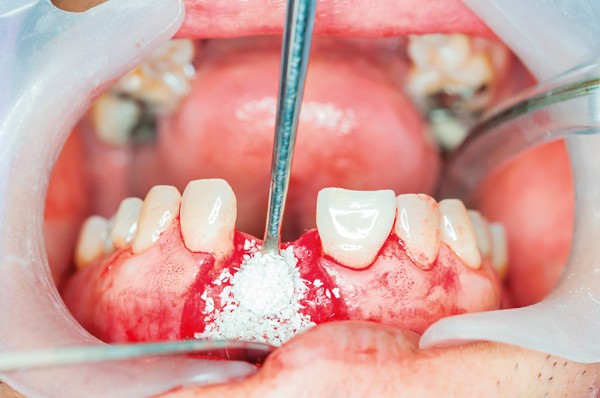

After the tooth is gently removed, the empty socket is carefully cleaned and filled with a bone grafting material. This material may come from the patient’s own body, a donor source, or synthetic alternatives. Once in place, the graft is typically covered with a protective membrane and sutured to secure the area.